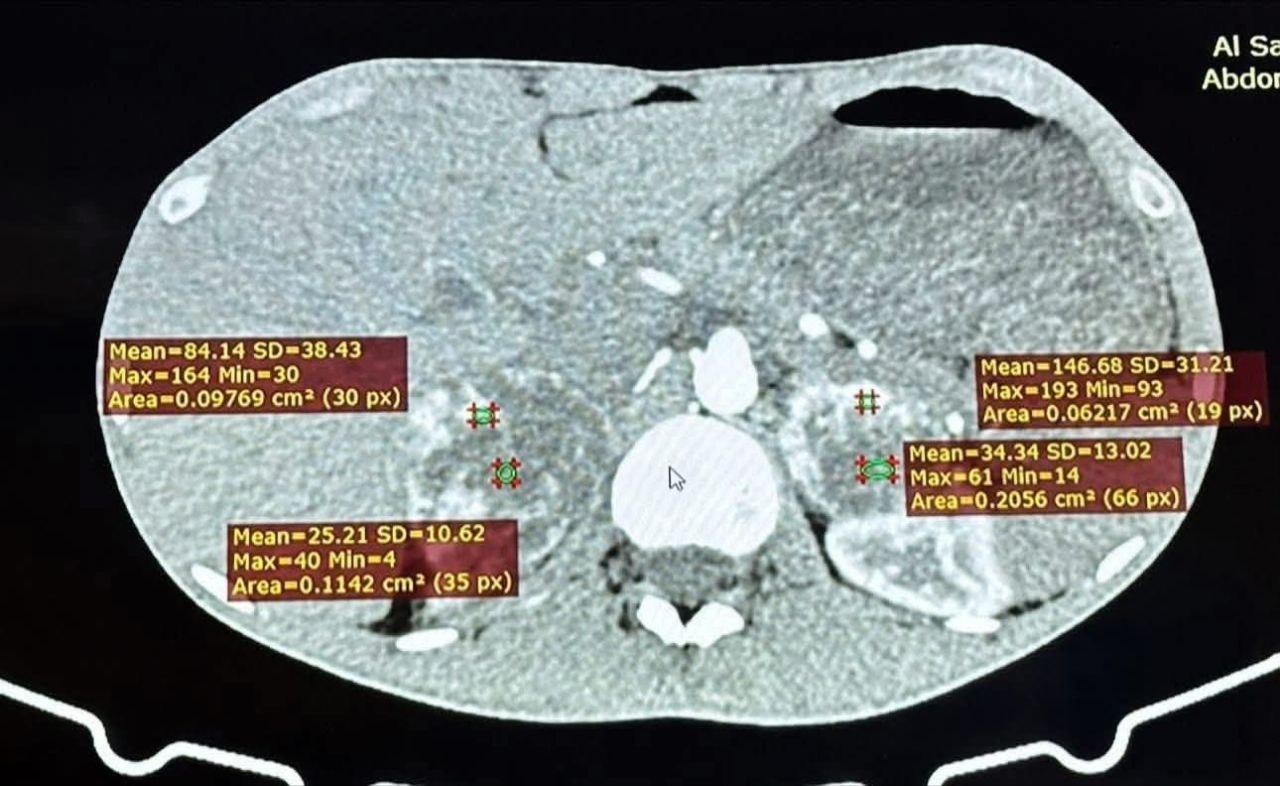

وتضمنت العملية استئصال الغدتين الكظريتين اليمنى واليسرى لمريض يبلغ من العمر (23) عاما من محافظة البصرة، كان يعاني من ارتفاع شديد في ضغط الدم وتسارع حاد في ضربات القلب، وبعد إجراء الفحوصات الطبية تبين وجود ورمين كبيرين في كلتا الغدتين الكظريتين يفرزان هرمون الأدرينالين بنسبة مرتفعة جدًا (Bilateral pheochromocytoma) مما شكل خطرا كبيرا على حياته.